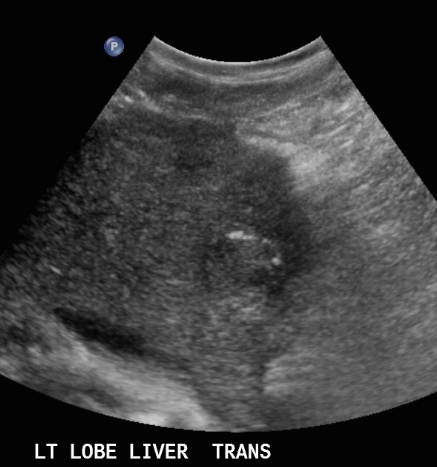

US finding

- 동일한 크기의 다발성 종괴가 나타난다.

- 고에코의 다발성 종괴: 대장암이 많으나 위암도 비교적 흔하다.

- 저에코의 다발성 종괴: 유방암, 폐암등에서 나타난다.

- 석회화나 내부 낭성 변성은 전이성 간종양을 시사하는 소견이다.

- bull's eys sign (종양 변연에 중심부가 고에코이고 경계부가 저에코인 두꺼운 띠가 보인다)

- cluster sign (종양이 융합하여 분엽모양을 이루어 마치 포도송이 모양을 나타낸다)